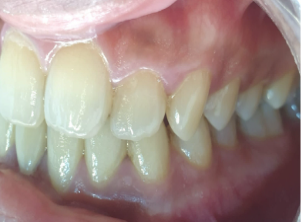

A comprehensive oral examination shows an Angles Class 1 molar relation with unilateral anterior cross bite. There was asymmetric overjet and overbite with anterior crowding in upper and lower arches.

The treatment plan utilized a non extraction approach to address the patient’s concerns. The primary goal was to correct maxillary anterior crossbite along with relief in both upper and lower arch crowding. Furthermore, the treatment aimed at achieving symmetric overjet and overbite.

This orthodontic treatment utilized 15 sets of Illusion aligners over a 5-month period. Illusion aligners were crafted from advanced materials making them invisible during wear. These aligners were designed to gradually reposition the upper right lateral incisor and align the lower anterior teeth, keeping the treatment objectives in mind.